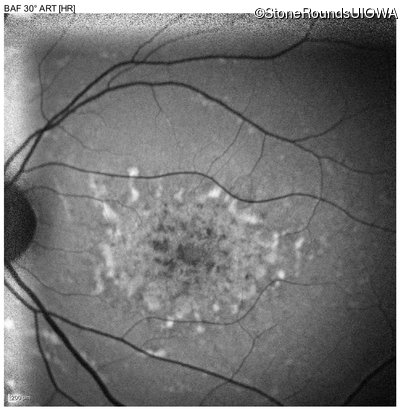

Age at visit: 22 years

This 22 year old woman first had difficulty seeing the blackboard at age 14 and this was not correctable with glasses.

Age at visit: 17 years

Age at visit: 18 years

Age at visit: 19 years